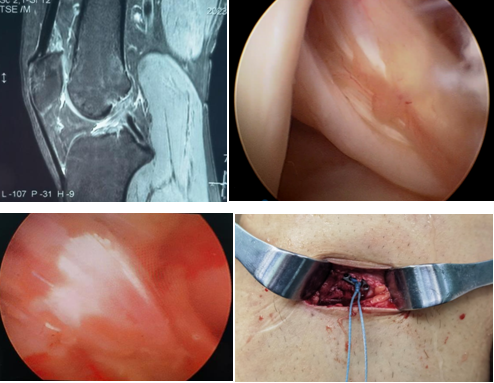

近日,一名31岁男性因打篮球扭伤致“右膝关节疼痛伴行走不稳半年”入院,术前诊断:前交叉韧带部分断裂。考虑患者年轻且有较高的运动恢复需求,在骨科病院刘时璋主任医师的指导下,由冯敏副主任医师主刀完成三级片

首例关节镜辅助下前交叉韧带损伤“保残+全内”重建术。患者第二日即下地活动,第三天顺利出院。

ACL的保残重建具有有效促进ACL移植物血管再生,促进损伤ACL本体感觉的恢复,以及防止ACL术后隧道扩大等多种技术优势。而ACL的全内重建技术是国际上新近发展出现的另一项新技术,相比传统方法,它仅需获取自身单根肌腱,而且所需长度远小于传统重建方法。另外,此技术保留了更多的骨皮质及骨膜,术后疼痛更少,腱骨愈合更佳,同时有效降低了术后感染风险,避免了传统方式界面螺钉对肌腱的切割作用。